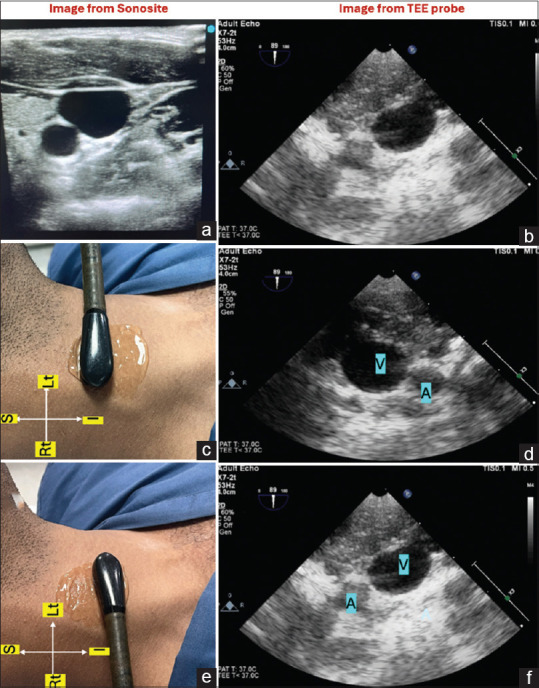

Comparison of Transesophageal Echocardiography Probe as Surface Probe with Vascular Probe During Right Internal Jugular Vein Catheterization in Cardiac Surgeries.

经食管超声心动图探头作为表面探头与血管探头在心脏手术右颈内静脉置管中的比较。